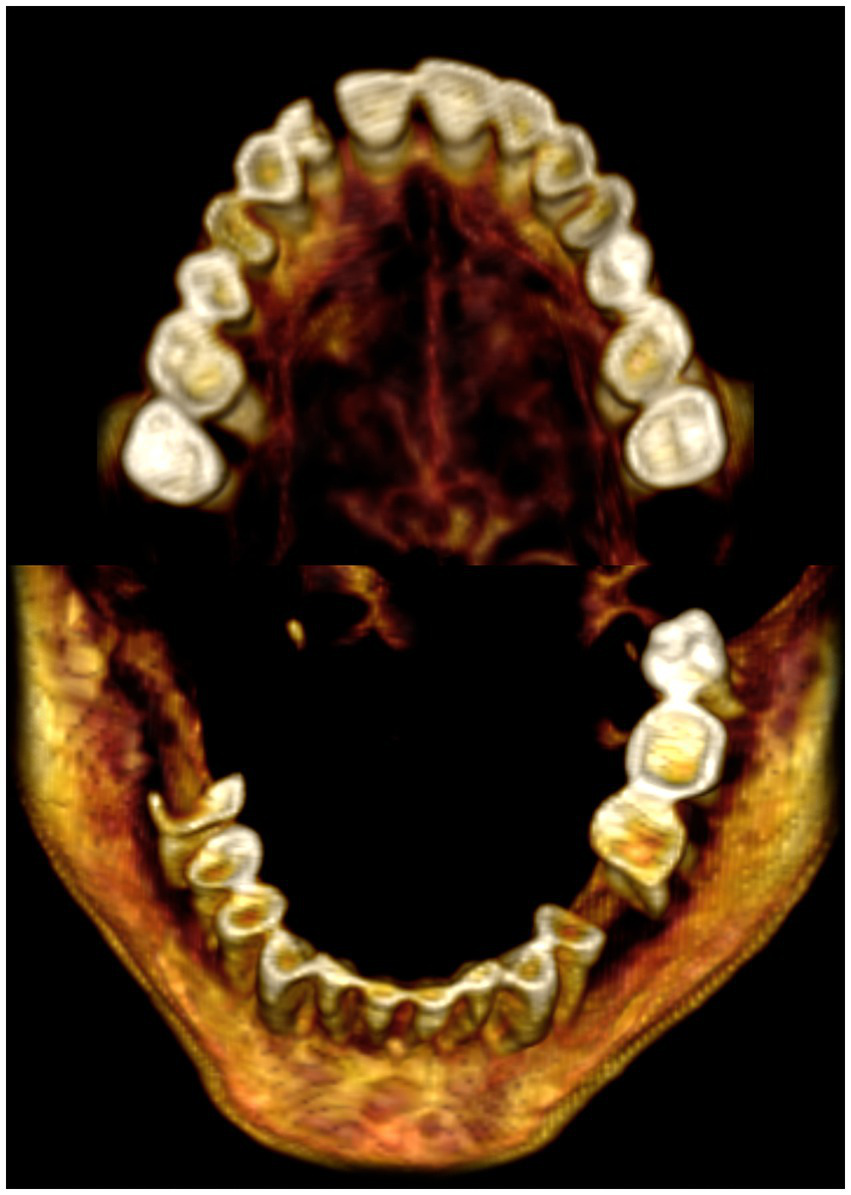

Evidence of mild to moderate teeth attrition. Ante-mortem missing of the following teeth: upper right third molar tooth, upper left third molar; second and third lower right molars and lower left second premolar tooth. There is evidence of bone loss (resorption) of the sockets of the missed teeth. Partially broken teeth: right upper lateral incisor and right lower first molar tooth. There was no evidence of periodontal disease or caries cavities (Figure 5).

Figure 5

A three-dimensional CT images of the maxillary and mandibular teeth of mummified woman (referred to as CIT8) show that some teeth were missing during life with signs of bone loss (resorption): upper right third molar, upper left third molar; second and third lower right molars, and lower left second premolar. Partially fractured teeth include the right upper lateral incisor and right lower first molar. Mild to moderate attrition of the remaining teeth with no signs of periodontal disease or caries cavities. The mummy CIT8 with a screaming face expression was discovered in Luxor, Egypt, near Senmut’s service tomb, the architect during Queen Hatschepsut’s reign (1479–1458 BC).

The widely opened mouth of mummy CIT8 enabled adequate physical inspection of tooth attrition, as well as broken and missing teeth. Reconstructed CT images of maxillary and mandibular teeth of mummy CIT8 showed with clarity broken teeth, missing teeth associated with bone loss (resorption), and attrition of the remaining teeth, which had been observed in physical inspection.

In previous studies, CT scanning proved beneficial in identifying the state of the teeth in ancient Egyptian mummies. Missing teeth, supernumerary teeth, attrition, peridontal disorders, and dental absecesses were detected using CT scans of mummies (6, 7, 11). However, there was no CT evidence of periodontal disease or caries cavities in mummy CIT8. The multiple missing teeth were most likely lost during life (ante-mortem) since there is evidence of bone resorption, which occurs when a tooth comes out and the socket is left to heal. It is unknown if the missing teeth in the studied mummy were intentionally removed or not. According to hieroglyphic records, the ancient Egyptians practiced dentistry. In fact, the world’s known first record of a dentist was Hesyre (about 2660 BC), a chief dentist in ancient Egypt (29). Some ancient human remains and mummy research have shown instances when teeth extraction may have happened in ancient Egypt (29–31); but other studies threw doubt on it (32). Further research and information on ancient Egyptian dentistry is required. According to preliminary research studies, ancient Egyptians appear to have more dental wear and decay than modern populations (33).